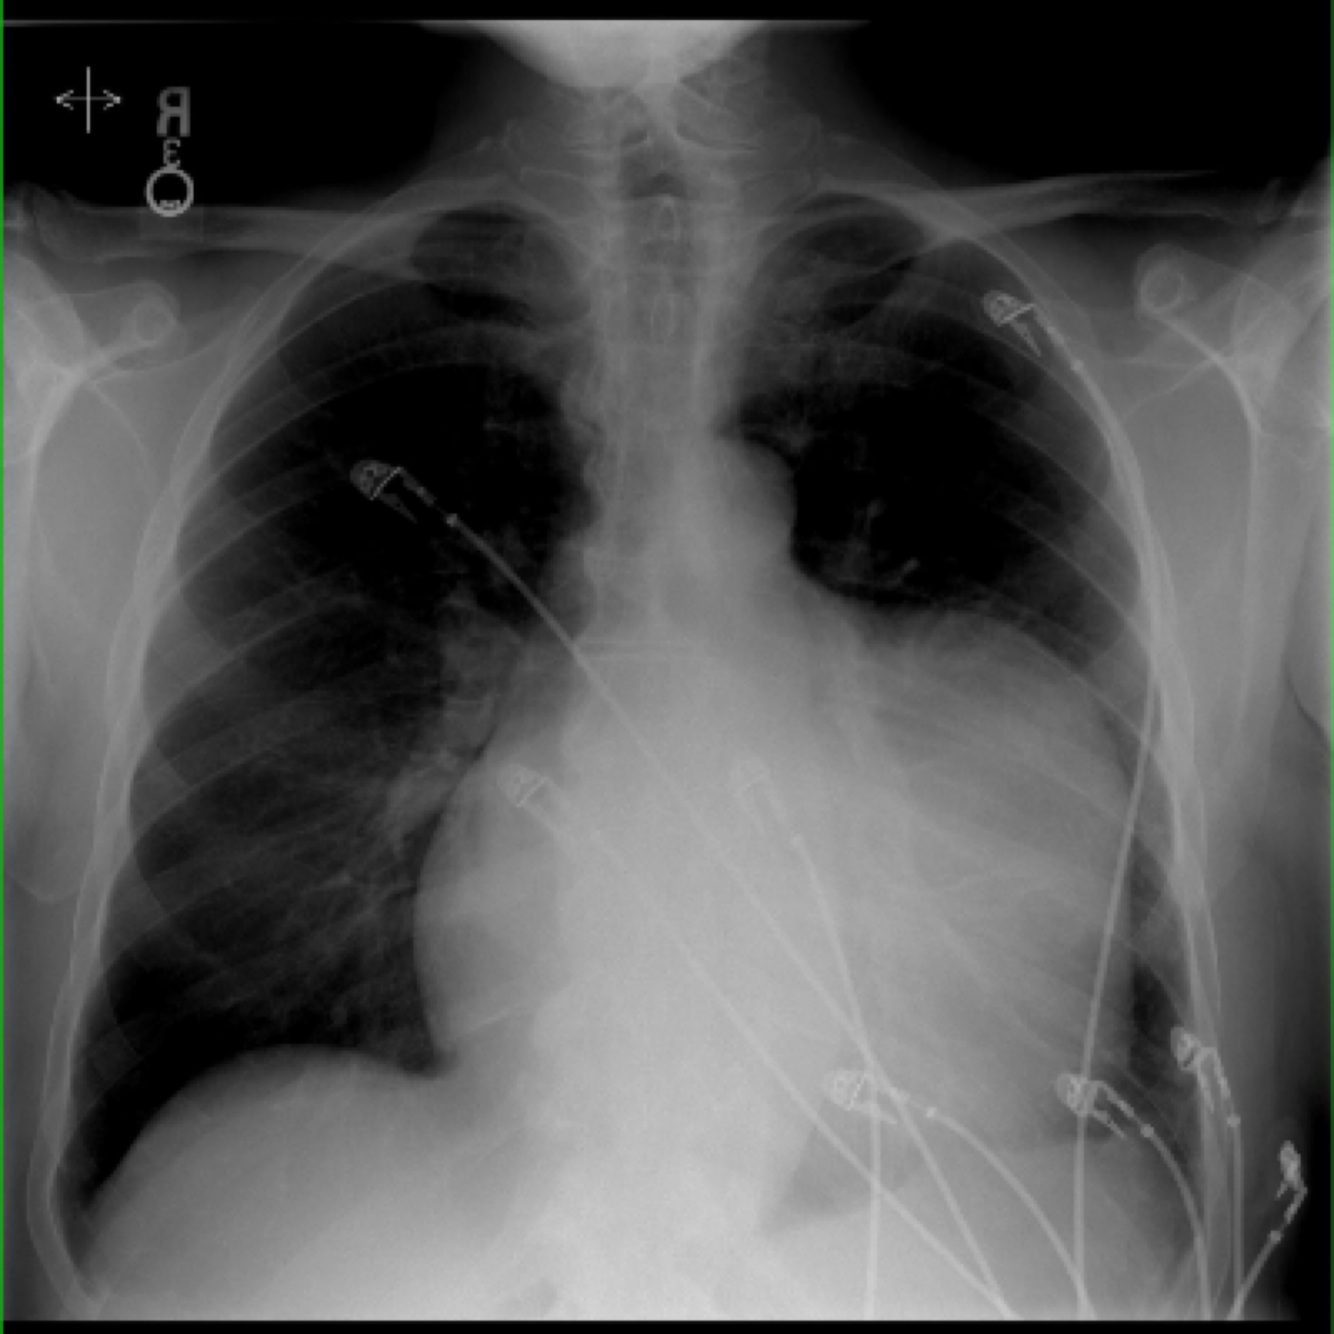

dilated cardiomyopathy